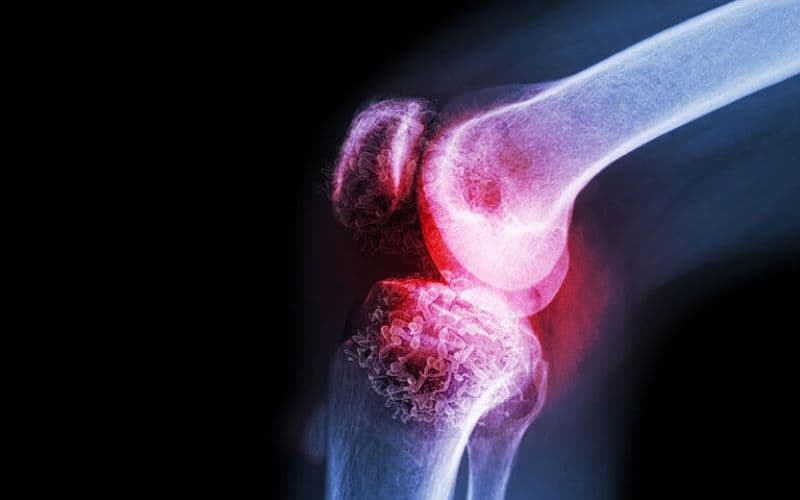

U xương lành tính là những khối u phát triển từ mô xương nhưng không có khả năng xâm lấn hay di căn như u ác tính.

Nhiều người vẫn băn khoăn liệu “u xương lành tính có đau không?” hay “u xương lành tính đau như thế nào?”- câu trả lời là có thể có hoặc không, tùy vào từng trường hợp cụ thể. Nhiều trường hợp u xương lành tính hoàn toàn không gây triệu chứng và chỉ được phát hiện tình cờ khi chụp X-quang sau chấn thương hoặc khám sức khỏe định kỳ. Tuy nhiên, cũng có những khối u gây đau với mức độ khác nhau tùy loại, vị trí và kích thước.

Về vấn đề “u xương lành tính đau như thế nào?” thì nhiều cơn đau thường âm ỉ, kéo dài, tăng dần theo thời gian. Một số trường hợp đau rõ hơn khi vận động hoặc khi khối u chèn ép vào mô xung quanh. Đặc biệt, u xương dạng sụn (osteoid osteoma) có thể gây đau dữ dội về đêm và giảm khi dùng thuốc kháng viêm không steroid. Nếu khối u làm xương yếu đi, người bệnh có thể đau đột ngột do gãy xương bệnh lý.

Trong nhóm u xương lành tính thường gặp như u sụn nội tủy, u sụn xương, u xơ không cốt hóa hay loạn sản xơ xương, phần lớn không gây đau ở giai đoạn đầu. Chỉ khi khối u phát triển lớn, ảnh hưởng đến khớp lân cận hoặc làm biến dạng, suy yếu cấu trúc xương thì triệu chứng đau mới xuất hiện.